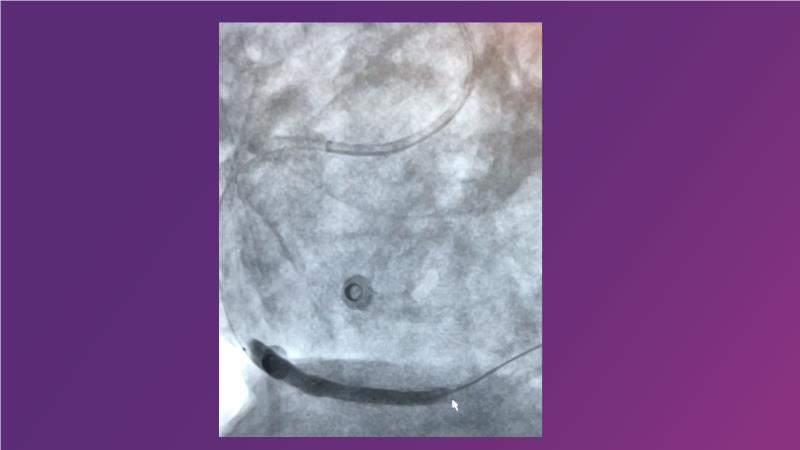

Tune into this 2024 session for insights into the latest ESC guidelines, strategies to prevent and treat no reflow, and an examination of trials like TASTE, TAPAS, and TOTAL on coronary thrombus management. Explore also the outcomes of the CHEETAH study, pondering a potential paradigm shift, and delve into a case study on thrombus removal in a patient with high thrombus burden.